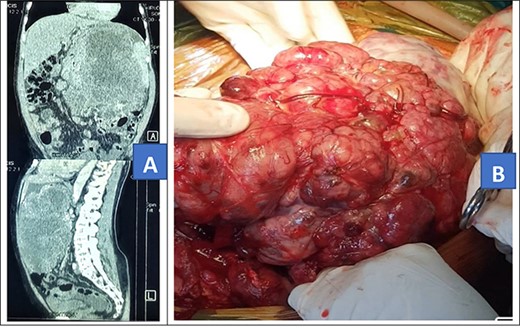

A 72-year-old African male presented with 10-month history of abdominal mass associated with early satiety, epigastric discomfort and weight loss. He had no history of any chronic illness and had a vague memory of his father’s grandmother being diagnosed with possible nasopharyngeal carcinoma and his uncle had radiotherapy for unknown brain tumor. On examination, he had a grossly distended abdomen with a firm mass in the left upper quadrant which was mildly tender. Other examination findings were unremarkable. Abdominal computed tomography (CT) scan done prior to admission showed a giant solid retro gastric mass involving part of the greater curvature of the stomach, spleen and part of the distal one-third of the transverse colon (Fig. 1A). The patient was scheduled for open surgery.

Contrasted abdominal CT scan (A) and intra-operative picture (B) for Patient 1.

Intra-operatively, a giant left upper quadrant tumor was found to be infiltrating and involving the spleen, greater curvature of the stomach and transverse colon (Fig. 1B). The tumor was mobilized from its retroperitoneal attachment, the splenic vessels were ligated and the entire tumor removed. Partial gastrectomy was done for the involved part and a 20-cm long distal transverse colectomy was done and a double barrel colostomy fashioned. The patient lost 1500 ml of blood and was transfused with two units of whole blood intra-operatively. The tumor was taken for histology and the results showed atypical pleomorphic spindle-shaped cells with abnormal mitosis. Immunohistochemistry: cells were positive for CD34 and CKIT which is in keeping with gastrointestinal stromal tumor.